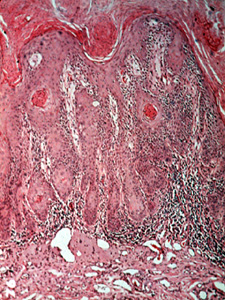

| Las cortes microscópicas de la queilitis actínica

muestra mucha queratina en la superficie

Con alargamiento de la basal formando lomas y debajo

se observs el tejido conjuntivo inflamado |

| Una vista a más aumentos muestra las anormalidades celulares similares a aquéllas

descriptas en el displasia de la mucosa, dilatación vascular y degeneración del colágeno

extensa ("elastosis senil"). Éstas son las alteraciones debido a la radiación solar. |

| Se muestran inflamación crónica, "elastosis senil" y displasia del

epitelio con oscuridad anormal agrandada de los núcleos más mitosis,

con este poder de resolución, en la queilítis actínica. |